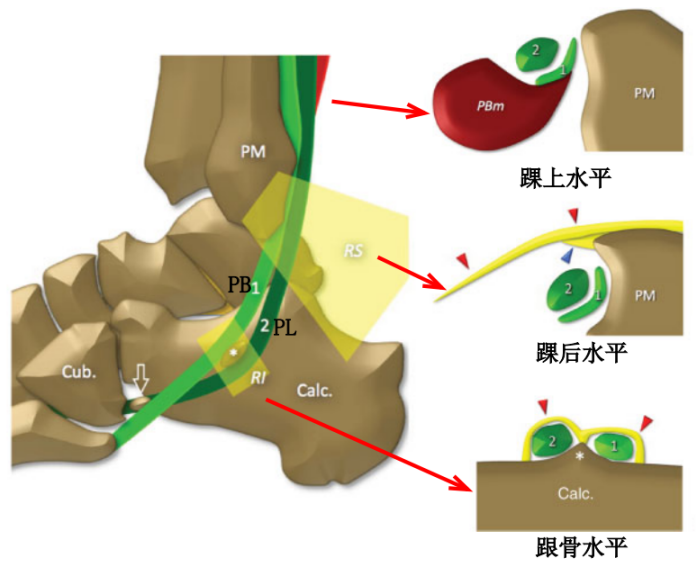

腓骨长肌(PL):起于腓骨头、腓骨外侧面上2/3和小腿深筋膜,止于第1跖骨外侧及毗邻的第1楔骨的内侧,至小腿下1/3处,长肌移行为肌腱,在它到达止点前的行程中有三个弯曲,第一个在外踝顶点,第二个在跟骨外侧壁的腓骨肌滑车下,第三个在骰骨结节处经90°转到足底。

腓骨短肌(PB):起于腓骨外侧面下2/3及前后肌间隔,短肌至外踝的后下方始为移行为肌腱,紧贴于外踝后方,通过外踝顶点转向足外侧前方,经过跟骨外侧壁腓骨肌滑车上方最后止于第五跖骨基底。

腓骨外踝窝:外踝的后方近端较宽广,远端呈锥形变小并有一浅的沟。

纤维软骨脊(FCR):腓骨外踝窝的外侧缘有一纤维软骨形成的缘,构成了窝的结构。该纤维软骨脊近端明显,向远端渐变小,使得沟的整体深度增加了2-4mm,且形状更适于容纳腓骨肌腱,从而促进应力分散。

Raikin等学者提出将腓骨沟内腱鞘内半脱位不伴有腓骨上支持带损伤划为腓骨脱位的亚系。这些腱鞘内半脱位共有两型:

A型:腓骨肌腱无撕裂,肌腱暂时换位;

B型:腓骨短肌存在纵向撕裂,腓骨长肌腱自撕裂处半脱位。